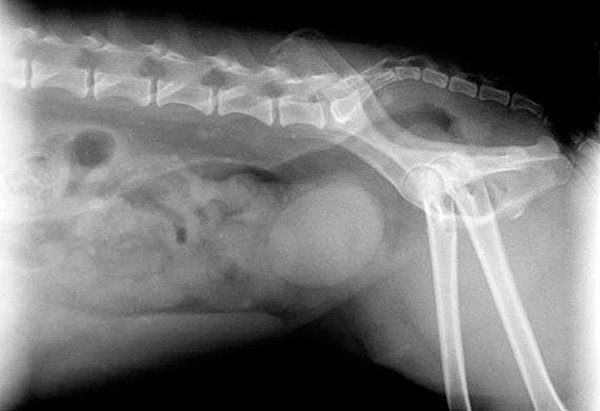

radiografia-prostata-perro

El veterinario, mediante un examen rectal, puede detectar si una próstata se presenta agrandada o no. En esta revisión el profesional detecta, además del tamaño, la posición y la consistencia de la glándula. La ecografía es una prueba que también proporcionará información.